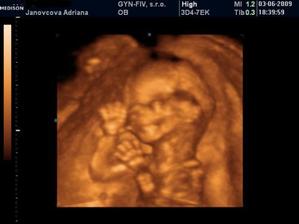

3.6. Uzasny 3D ultrazvuk...Videli sme nasho mimiska... Meriame bez noziciek 10 cm a s nozickami skoro 15 cm... 🙂 A doktor nas prekvapill, ze vraj to bude chlapcek... 🙂 14.7. morfologicky ultrazvuk, vsetko zatial vyzera v poriadku - tesime sa na Andrejka 🙂 12.8. 3D ultrazvuk - ma to 35 cm a 900 gramov, kto je to? No predsa ja Andrejko... 🙂